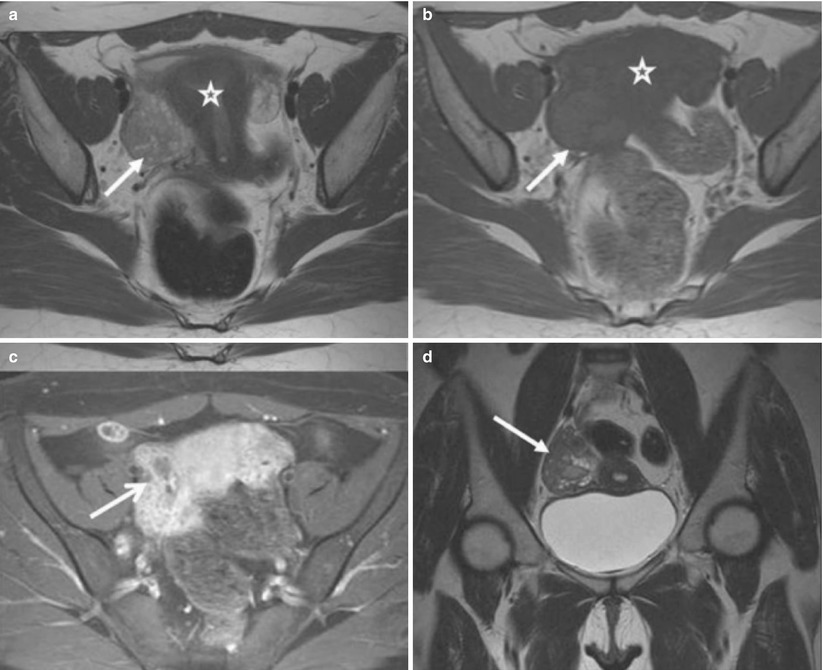

From www.researchgate.net

CT Findings of Periappendiceal Inflammation and Pelvic Inflammatory Tampons Pelvic Inflammatory Disease pelvic inflammatory disease (pid) is defined as an. pelvic inflammatory disease (pid) is an infection in the pelvis. Pid usually begins in the fallopian tubes and may infect the. pelvic inflammatory disease can produce acute symptoms and result in infertility, ectopic pregnancy, and chronic pelvic pain. pelvic inflammatory disease (pid) refers to acute and subclinical infection. Tampons Pelvic Inflammatory Disease.